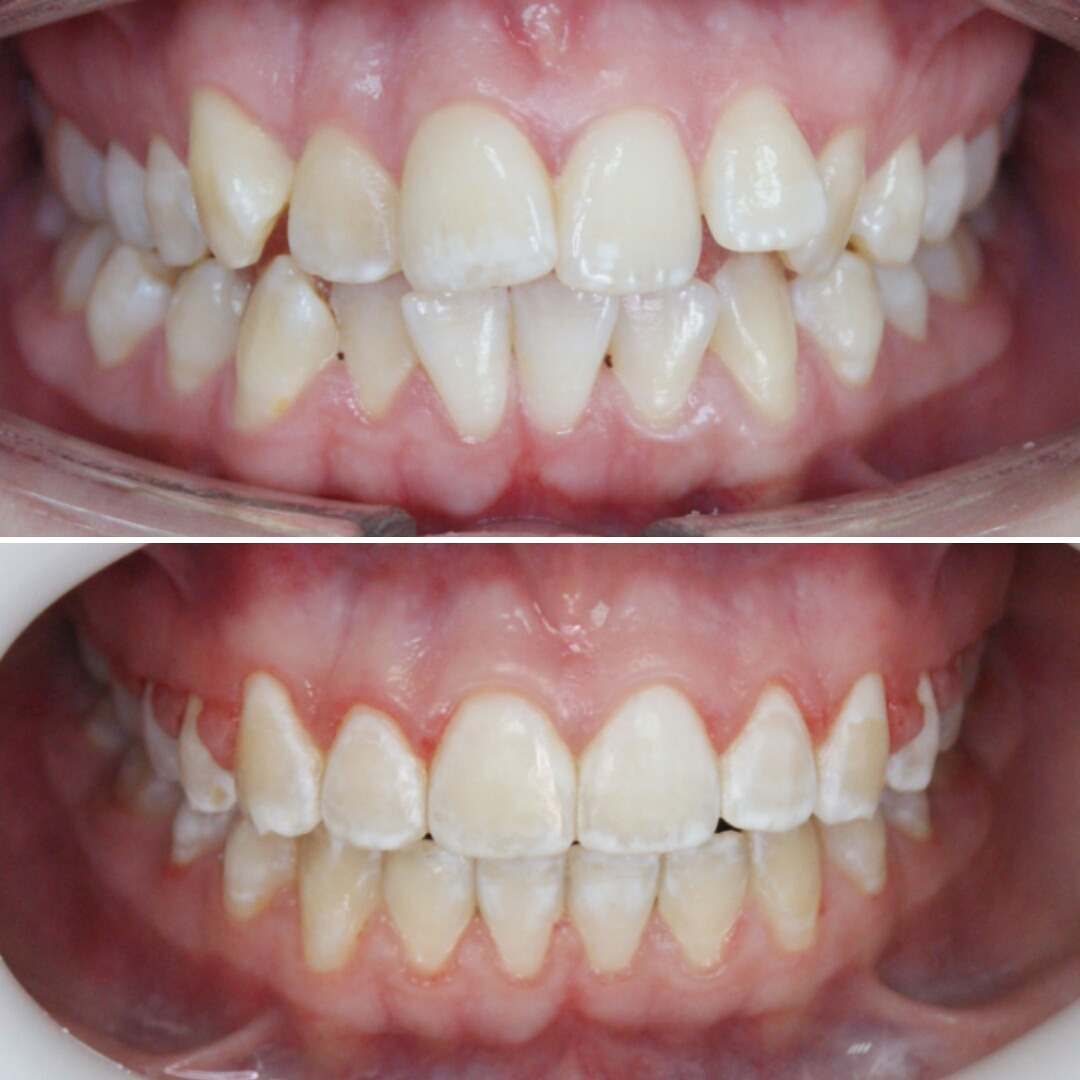

Большое путешествие зубов на своё законное место.

Эта фраза знакома многим ответственным родителям, которые привели на приём к ОРТОДОНТУ своего ребёнка в 5-10 лет, заподозрив проблему или понимая, что места постоянным зубам откровенно не хватает! Горькая правда в том, что брекеты - не волшебное средство от всех проблем, они "расставляют" зубы внутри сформированого объёма челюсти, но никак не влияют на её рост. Родители ждут, а тем временем драгоценное время, когда ребёнок растёт, уходит... Во взрослом возрасте приходится удалять здоровые зубы или прибегать к ортогнатической хирургической операции. 📸 На фото узкая нижняя челюсть, места постоянным зубам нет, боковые резцы прорезываются "вторым рядом".

❓Ну что? Будем ждать 12 лет? Или будем помогать ребёнку?

✅ Помогаем с помощью расширяющей дуги, пружины и зацепных элементов, которые зафиксированы на МОЛОЧНЫЕ зубы